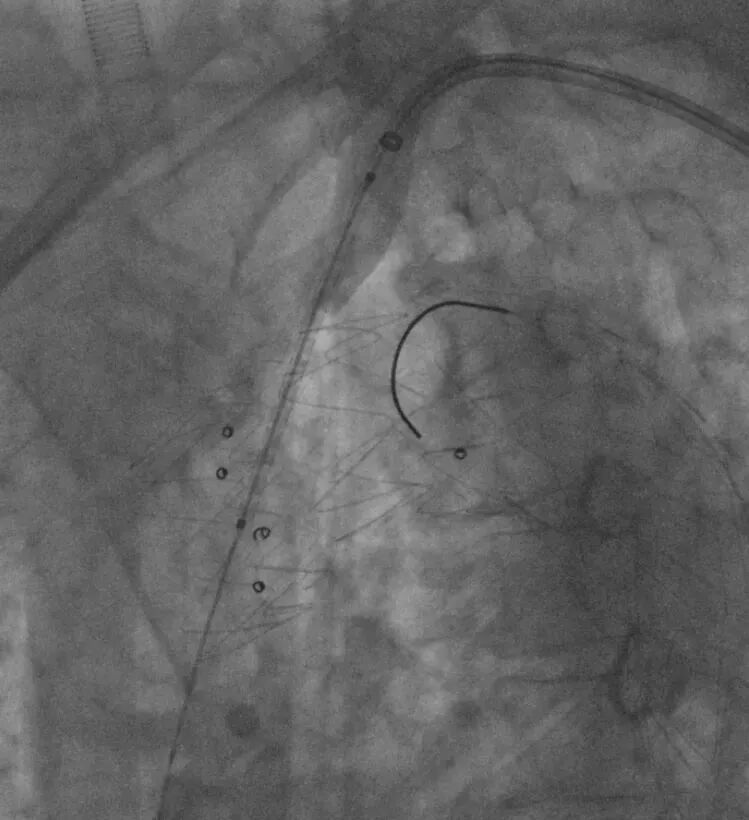

3. 经左肱动脉鞘管引入单弯导管,头端正对于主动脉弓处覆膜支架,置入250T导丝并配合单弯导管,顺利在左锁骨下动脉根部处原位开窗,手推造影明确导丝已进入覆膜支架。

送入单弯导管及250T导丝

250T导丝成功于LSA根部破膜

4. 依次使用3-30mm球囊、8-40mm球囊扩张开窗口;并通过球囊带鞘技术通过主动脉开窗部位。

3-30mm球囊扩张

8-40mm球囊扩张

RAO确认

球囊带鞘进膜